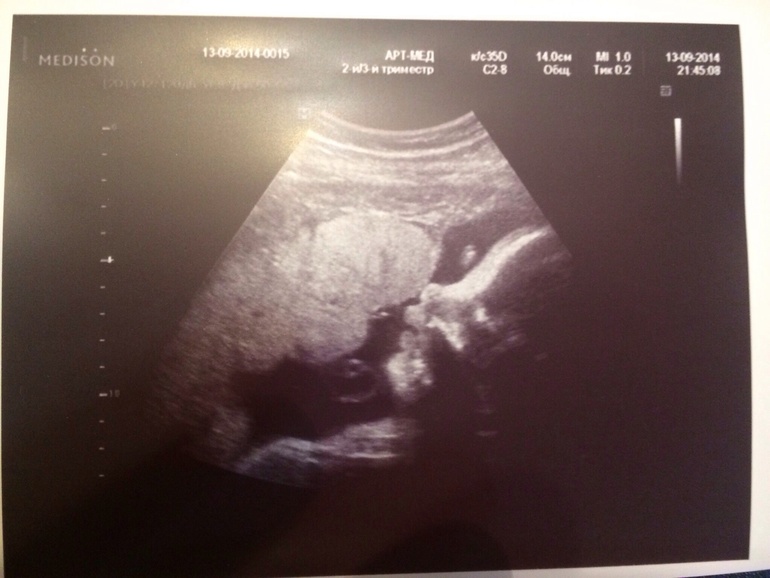

Вчера были на УЗИ!!!

Наш любимый мальчик так вырос!!)))

Лежал зевал, открывал ротик и как всегда закрывался ручками!!

Губы большие такие, как у мужа, волосики отросли длинные!!!)))

Весим 1884 г., все у нас хорошо, плацента только ей не очень понравилась!

Одно обвитие, говорят все свободно вокруг шеи и малышу это не мешает!

Лежим головой вниз, как я и думала, что сынуля бил меня ножкой вверх!!))